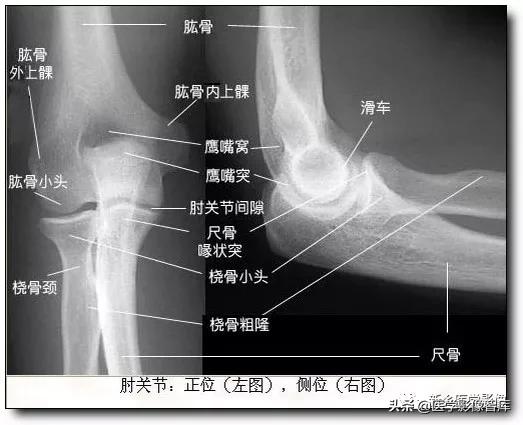

肘关节的X线解剖肘关节常规X线片包括伸肘前后位及屈肘90°的侧位(图1)。正位像肱桡关节间隙清晰,呈下凹的浅弧形;肱尺关节间隙有尺骨滑车切迹重叠而变暗,呈上凹的弧形,故而正位片上肘关节间隙呈波浪状。屈肘侧位片,肱尺关节间隙清晰,呈半环形,前为冠突,后为鹰嘴。肱桡关节掌侧清晰,背侧部分和尺骨冠突相重叠。此时通过桡骨纵轴线的延长线也穿过肱骨小头中心。

伸肘正位片上,肱骨、尺骨长轴线形成向外165°~170°的夹角,此为生理性前臂外翻角,男性一般大于女性。若小于l65°叫肘外翻,大于190°叫肘内翻,如果是180°则叫直肘(图1-1),均属异常表现。肱骨长轴与尺骨长轴在内下方的夹角谓之提携角,正常范围5°~20°之间,女大于男。